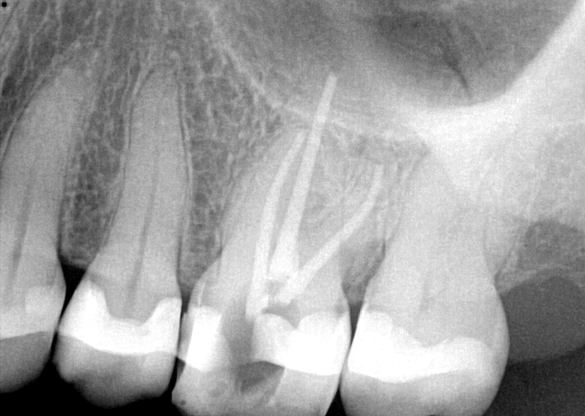

Fig 7. Primary endodontic and secondary periodontal lesion, mandibular second molar.

Figure 7

Fig 8. Gold crown removed, dentin excavated, canals shaped and filled.

Figure 8

Fig 9. 33 days postoperative fiber-post placement and CAD crown.

Figure 9

Treatment of combined endodontic and periodontal lesions does not differ from the treatment of either an endodontic lesion or a periodontal lesion. The part of the lesion sustained by the root-canal infection can usually be expected to resolve after proper endodontic treatment. Timing of the completion of the root-canal therapy, medicaments used, and assessment of restorability are considerations for the long-term success and survival of the tooth.7 Figures 7, 8, and 9 represent the timing of completion and restorative decision-making to complete all therapies.

In Figure 7, the periapical radiograph identifies the presence of the combined endodontic-periodontal lesion developing due to a carious lesion beneath an existing vintage gold crown with ill-fitting margins. Intraoral examination revealed a fistula developing and moderate pain on percussion and mastication. After occlusal access and clear visualization of the canals, the canals were shaped using the rotary files, with precautions taken not to perforate or enlarge the apical foramen. Maintaining the endodontic therapy within the canals prevents the infection from being introduced into the surrounding periodontium. In this case, calcium hydroxide medicament was placed into the canals and evaluated 30 days postoperatively.8

The patient returned for final evaluation of the provisional calcium-hydroxide endodontic therapy and resolution of the infection (33 days postoperatively). Fistula was not present; the tooth was not sensitive to percussion or mastication. The gold crown was removed using a high-speed metal cutting bur, the remaining caries were excavated conservatively, and the endodontic therapy was completed. Placement of glass-fiber reinforced composite and composite core buildup took place. The natural tooth structure to receive the glass-fiber post and a long-term restoration was available (Figure 8). Within one appointment, the tooth was restored (Figure 9). The patient was instructed to return for clinical and radiographic evaluation after 6 to 12 months to determine progression of periodontal healing. At that time, if the healing were adequate and the tooth were stable, evaluation of the tooth would be considered every 3 to 4 years.7